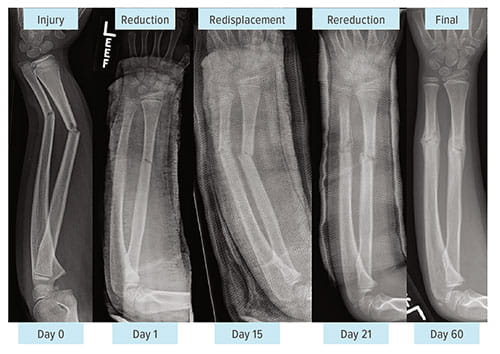

Rereduction Proves Effective, Reduces Cost of Treating Both-Bone Forearm Fractures in Children

Forearm fractures of both the radius and ulna can be treated with a less invasive, more conservative approach called rereduction—a procedure that is as effective as surgery but delivers up to 50 percent cost savings.

The approach involves a second re-setting of fractured bones that have lost alignment several days after being initially manipulated into position and placed in a cast. In about 25 percent of cases, fractured bones misalign as they heal, which typically prompts surgical treatment using nails or plates to stabilize them.

Re-aligning the bones and applying a second cast produced satisfactory radiographic outcomes in 87 percent of cases. The average cost of treatment was $2,056, compared to $4,589 for surgery.

"The second reduction was able to hold the fracture in place in a very good, very stable position,” Parikh says. “Previously, the conventional wisdom was that if initial reduction in the emergency department failed, it would not hold if we reduced it again. We proved that the bone does hold.”